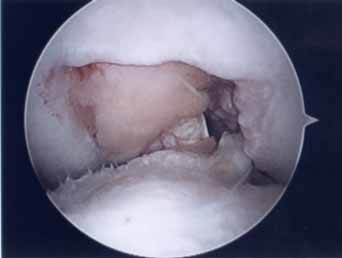

第3段階軟骨形成術

第2段階からさらに進行するとより広範囲の軟骨障害になりさらに軟骨の障害も深くなります。この段階ではドリリング手術を加えることが多くなります。第3段階ではまだ人工関節は適応はありませんのでできるだけ軟骨形成術をして膝の痛みを軽減し少しでも長く自分の膝で歩けるようにが目的です。本手術の結果は平均60~80点で患者の満足度は比較的高いので手術は安心下さい。

高度軟骨障害

高度軟骨障害では一般に人工関節が適応になります。しかし人工関節を行うにはまだ早い方、または一度この手術を行いできるだけ人工関節手術を先延ばしさせることを意図して、軟骨クリニーニング手術(第3段階手術の広範囲版)を行います。手術結果は50~75点くらいあり術後5~20年人工関節を先延ばしすることができます。全ての軟骨形成術後にはヒアルロン酸注射やPRP治療が推奨されます。